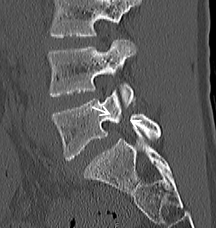

【術前】

CT検査で関節突起部に腰椎分離症を認めています。若年者の腰痛の原因となります。

【術後】

CT検査で関節突起部の骨移植を伴う分離部修復術を施行し骨癒合が得られています。